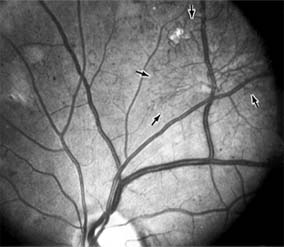

Diabetic retinopathy is a progressive microangiopathy characterized by small vessel damage and occlusion. The earliest pathologic changes are thickening of the capillary endothelial basement membrane and reduction of the number of pericytes. Background diabetic retinopathy is a clinical reflection of the hyperpermeability and incompetence of involved vessels. The capillaries develop tiny dot-like outpouchings called microaneurysms, while the retinal veins become dilated and tortuous (Figure 10-20).

Figure 10-20

Figure 10-20: Background diabetic retinopathy with abundant macular exudate (open arrow), micro-aneurysms (small arrow), and intraretinal hemorrhage (large arrow).

Multiple hemorrhages may appear throughout different levels of the retina. Flame-shaped hemorrhages are so shaped because of their location within the horizontally oriented nerve fiber layer, while dot and blot hemorrhages are in the deeper retina, where cells and axons are vertically oriented.

Macular edema is the most frequent cause of visual loss among patients with background diabetic retinopathy. The edema is caused primarily by a breakdown of the inner blood-retinal barrier at the level of the retinal capillary endothelium, allowing leakage of fluid and plasma constituents into the surrounding retina. The edema may be focal or diffuse and appears clinically as thickened, cloudy retina with associated microaneurysms and intraretinal exudate. Circinate zones of yellow, lipid-rich exudate may form around clusters of microaneurysms and are most frequently centered in the temporal portion of the macula. While the prevalence of macular edema is 10% in the diabetic population as a whole, there is a dramatic increase in prevalence in eyes with more severe retinopathy.

With progressive microvascular occlusion, signs of increasing ischemia may be superimposed on the picture of background retinopathy and produce the clinical picture of preproliferative diabetic retinopathy. The most typical findings here are multiple cotton-wool spots, beading of the retinal veins, and irregular segmental dilation of the retinal capillary bed (intraretinal microvascular abnormalities). Closure of retinal capillaries surrounding the foveal avascular zone may cause significant ischemia, manifest clinically by the presence of large dark retinal hemorrhages and small thread-like macular arterioles. Eyes with macular edema and significant ischemia have a poorer visual prognosis-with or without laser treatment-than eyes with edema and relatively good perfusion.